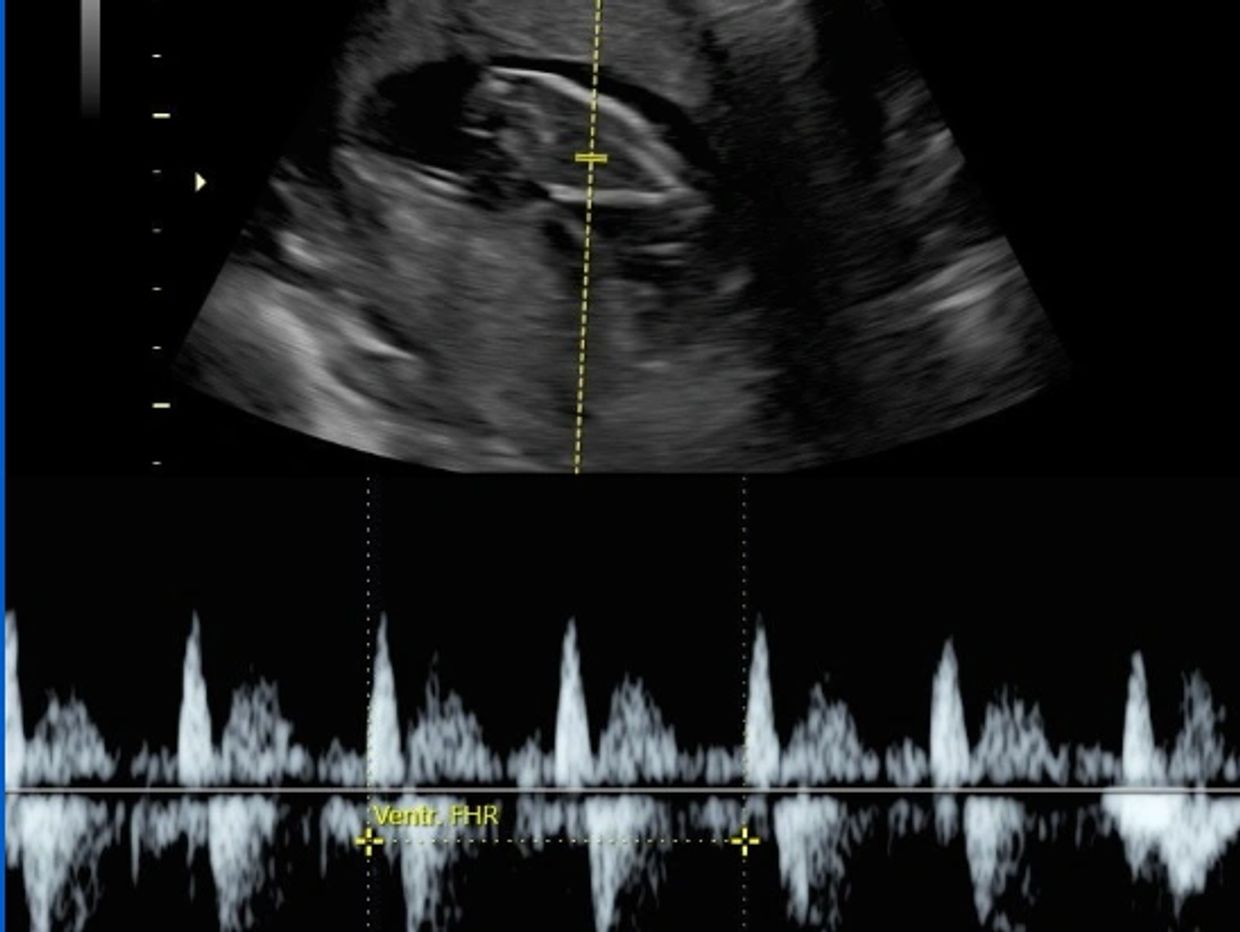

The closest ER was just one mile down the road. WHAT A BLESSING. I walked in and told them I was 7-8 weeks pregnant and that I was bleeding. They took me into a room, and I spoke with about seven different staff members to collect personal information, medical information, billing information, pregnant history information, etc. About 45 min later, they wheeled me into an ultrasound room. My technician was very nice, but when she pulled up the baby on the screen, I asked her,

“Is it alive? And she said “I can’t say, I am not the doctor.” I WANTED TO FLIP!!!!!! I had to get creative, so I said “is it moving?” And she said she couldn’t say.

But then she told me to “hold my breath” so she could “measure the heart rate!!” I’m like BINGO!! I said, “so there is a heart rate??” And she told me it was 165. The baby was alive, healthy, and doing just fine. Joe kept leaving the field and checking on me by calling from the clubhouse.

After the ultrasound, a nurse came in and told me there was a small hemorrhage that caused the bleeding, and the blood from today was most likely leftover from the implantation weeks before. They told me to wait 24 hours before traveling and schedule an appointment with my OB (which I don't have yet because we just moved). So I drove home, ordered food, and took it easy on the couch. I did not bleed the rest of the night, praise God.

May 6: 12-week appointment!! This one had me all kinds of excited!! This told us so much. The baby was significantly more developed, and Joe was with me at the ultrasound, which was so exciting. He hadn’t seen the baby moving on an ultrasound yet! The baby was doing summersaults and the head was so clear. The head is 1/3 the size of the entire baby right now. You could see the spine and the arms and the legs!!!